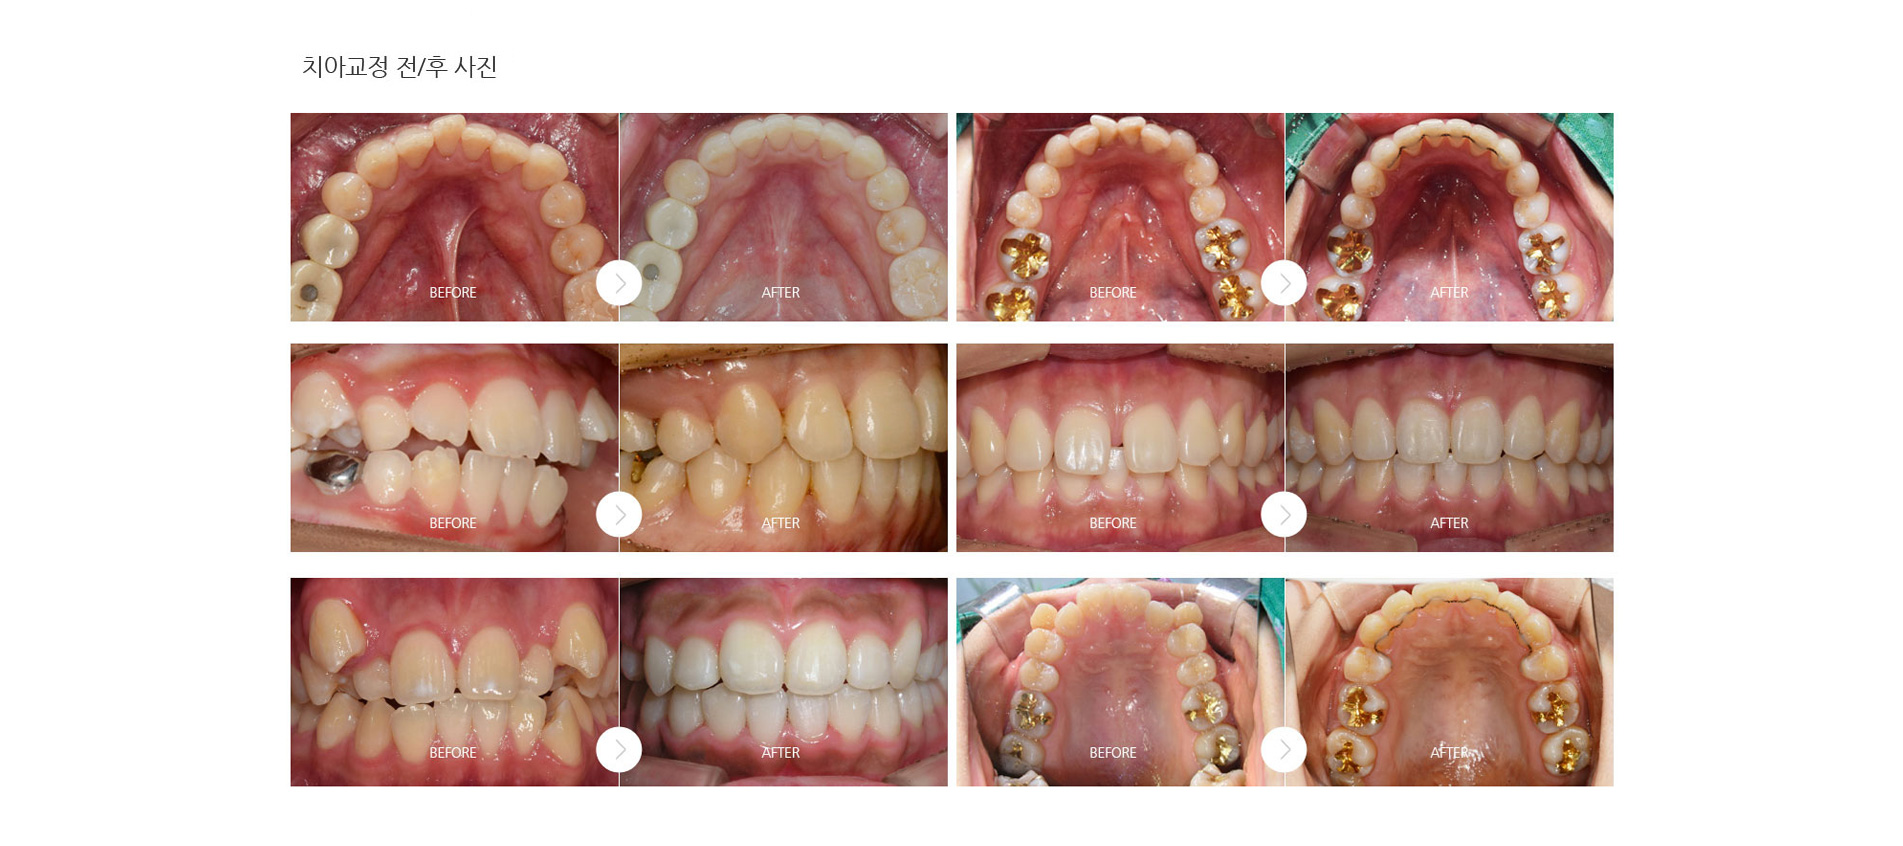

치과 치아교정 백년치과 디지털 교정 교정장치 재수술 임플란트 장치별 교정종류 온라인 상담 치아교정 전후사진 디지털 치아교정